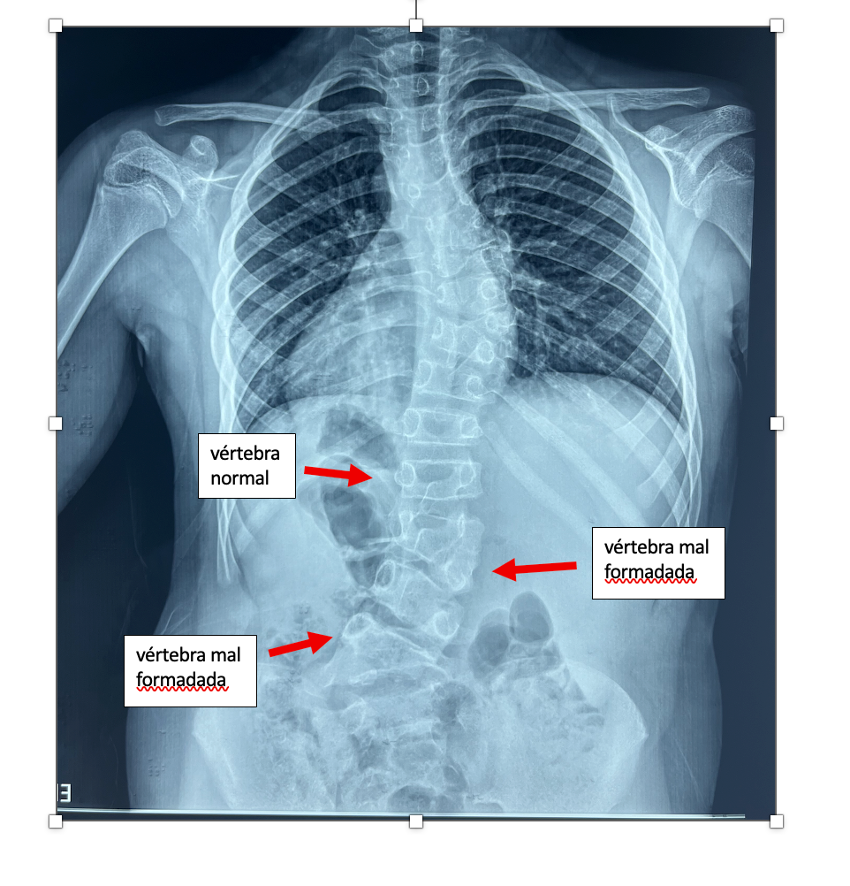

Escoliose congênita (falhas de formação ou segmentação vertebral)

Já a escoliose congênita é um tipo mais raro de escoliose, presente desde o nascimento. Estima-se que ocorra em aproximadamente 1 a cada 1.000 a 2.000 nascidos vivos. Ela se desenvolve porque, ainda durante a gestação, algumas vértebras não se formam adequadamente ou não se separam corretamente umas das outras.

Esse processo acontece muito cedo no desenvolvimento do bebê, quando a coluna ainda está sendo “construída”. Por esse motivo, a escoliose congênita não está relacionada à postura, uso de mochila, prática esportiva ou hábitos do dia a dia.

Como o problema está na estrutura óssea da vértebra, a curva apresenta algumas características típicas:

- não se corrige quando o médico tenta endireitar manualmente a coluna;

- não melhora com exercícios ou mudanças de posição;

- tende a ser mais rígida e menos flexível do que outros tipos de escoliose.

Para estes casos, a chance de progressão da curva ao longo do crescimento depende diretamente do tipo de anomalia vertebral presente. De forma geral, podem ocorrer dois grandes grupos de alterações:

- falhas de segmentação, quando as vértebras não se separam adequadamente;

- falhas de formação, quando a vértebra se forma de maneira incompleta ou assimétrica, como nas hemivértebras.

Cada um desses padrões apresenta um comportamento evolutivo diferente, o que torna essencial a avaliação individualizada.

Ressecção de vértebra malformada (hemivértebra)

Quando a deformidade está concentrada em uma vértebra específica malformada, pode ser indicada a retirada cirúrgica dessa vértebra (hemivértebra), seguida de uma correção localizada com fusão curta.

Essa abordagem busca tratar a causa da deformidade, permitindo boa correção da curva e preservando o máximo possível da mobilidade da coluna nos segmentos não acometidos.

Ao se considerar estudos cirúrgicos, obeserva-se que a ressecção posterior de hemivértebra com fusão curta é eficaz para correção de deformidades focais, com bons resultados em seguimentos de médio e longo prazo. Em contraste, deformidades congênitas mais extensas, envolvendo múltiplas anomalias vertebrais, tendem a exigir estratégias mais complexas e apresentam maior risco de progressão residual ou falhas mecânicas.